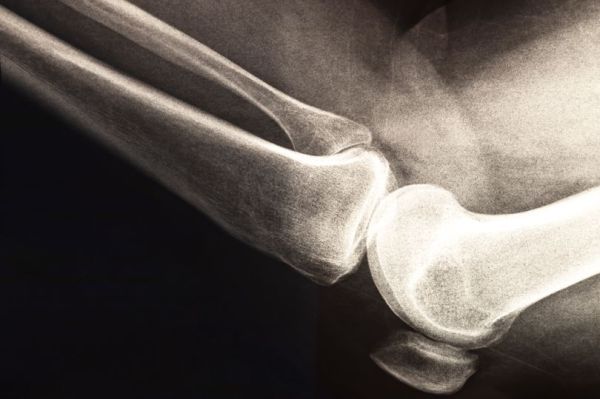

The research team followed nearly 10,000 women aged 65 and older over a decade to explore whether their daily habits of drinking coffee or tea were linked to changes in bone mineral density (BMD), a key indicator of osteoporosis risk. Osteoporosis is a major global health concern, affecting one in three women over 50 and contributing to millions of broken bones each year.

Evidence of the relative benefits or not of drinking tea or coffee has been mixed until now, with few studies having tracked the relationships over such an extended period. The Flinders University team analysed data from the Study of Osteoporotic Fractures, using repeated measures of both tea and coffee intake and BMD at the hip and femoral neck, areas strongly associated with fracture risk.

Over 10 years, participants reported their coffee and tea consumption, while researchers measured bone density using advanced imaging techniques. The findings, published in the journal Nutrients, showed that tea drinkers had a slightly higher total hip BMD compared to non-tea drinkers.

While the difference was modest, the research team said it was "statistically significant" and could have meaningful implications at a population level. Study co-author Professor Enwu Liu, of Flinders University's College of Medicine and Public Health, said: “Even small improvements in bone density can translate into fewer fractures across large groups."